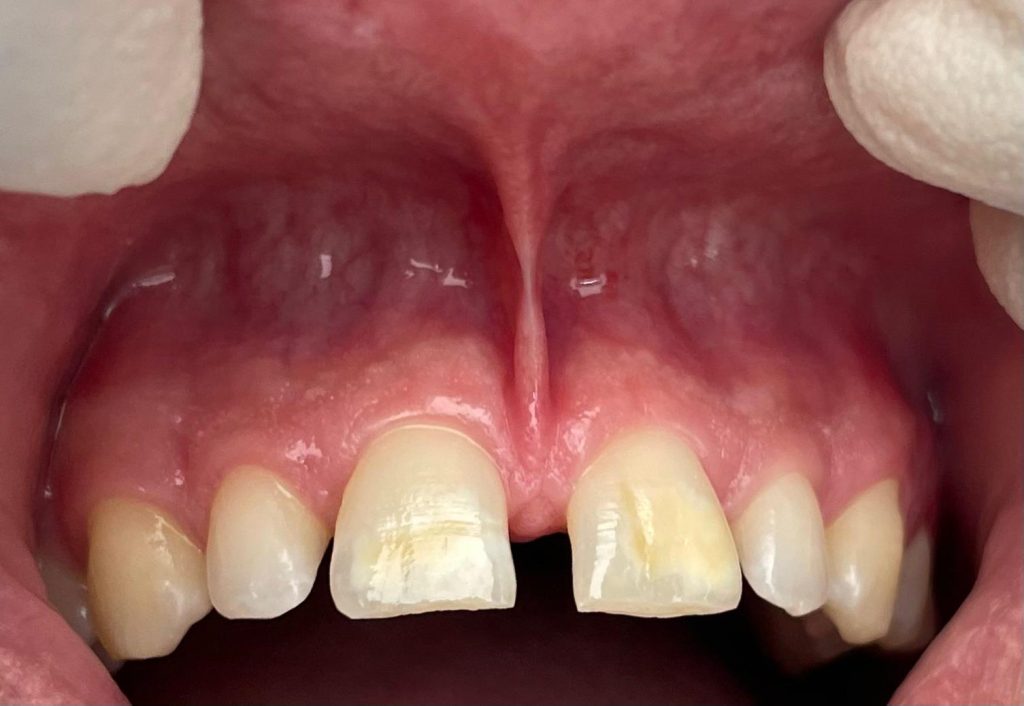

Questa settimana vi presentiamo il caso di frenulectomia del labbro superiore e inferiore eseguita con un laser KTP.

Nelle immagini, oltre alle fasi dell’intervento, è possibile osservare la guarigione dei tessuti dopo 10 giorni.